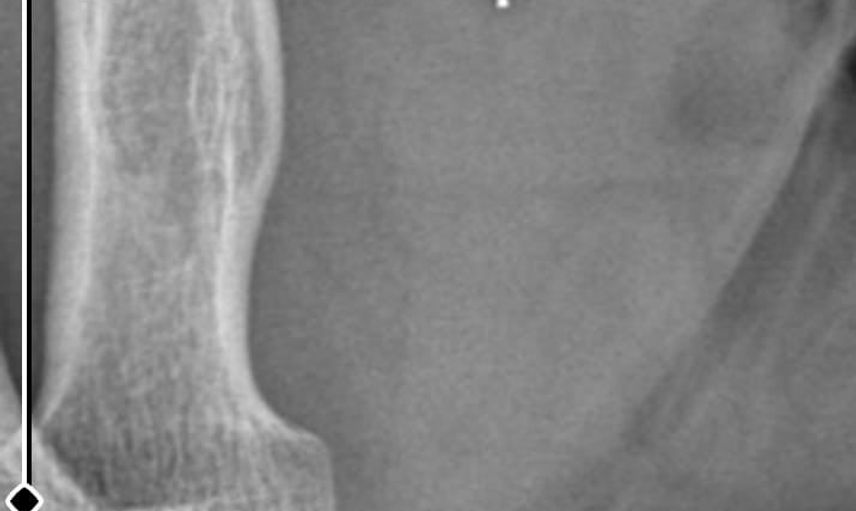

Ameliyatların ardından kolunda ağrılar hissettiğini söyleyen Güleryüz, kolunda metal parça bulunduğunu ve bu parçanın parmak bölgesinden dirseğe doğru ilerlediği iddiasını dile getirdi. Ayrıca çalıştığı fabrikada temizlik personeli olan Güleryüz'ün tedavi sürecinde işten çıkarıldığı öğrenildi.